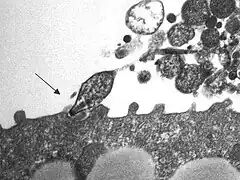

Description de l'image 1995dkdj,x.jpg.